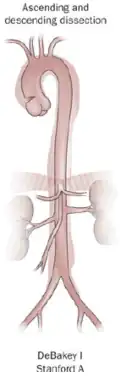

DeBakey

The DeBakey system, named after cardiothoracic surgeon Michael E. DeBakey, is an anatomical description of the aortic dissection. It categorizes the dissection based on where the original intimal tear is located and the extent of the dissection (localized to either the ascending aorta or descending aorta or involving both the ascending and descending aorta).[39]

- Type I – originates in ascending aorta, and propagates at least to the aortic arch and often beyond it distally. It is most often seen in patients less than 65 years of age and is the most lethal form of the disease.

- Type II – originates in the ascending aorta and is confined to it.

- Type III – originates in the descending aorta and rarely extends proximally, but will extend distally. It most often occurs in elderly patients with atherosclerosis and hypertension.